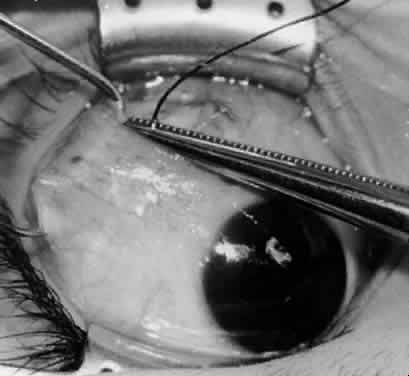

Fig. 14. The inferior temporal vortex vein, 8 mm posterior to the temporal insertion of the inferior rectus muscle, is held on a Green muscle hook.

Fig. 15. The placement of sutures within the sclera for a recession procedure of 10 mm. The anterior suture is placed 3 mm temporal and 2 mm posterior to the lateral insertion of the inferior rectus muscle, and the posterior suture is placed 3 mm further posteriorly.

Fig. 16. Two sutures straddle the inferior temporal vortex vein insertion for a 14-mm recession procedure.